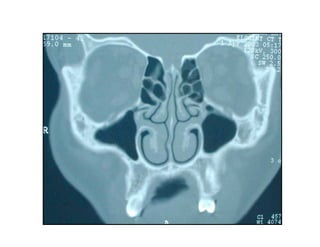

Este documento describe los principios de construcción de la arquitectura craneofacial, incluyendo el metamerismo, la simetría y la paquimería. Explica la organización peri-cavitaria del cráneo a través de columnas y vigas, y analiza las diferentes fascias profundas del cuello. También destaca la importancia de conocer la irrigación ósea con orientación quirúrgica, mencionando los principales aportes vasculares y suplementarios así como el origen, trayecto y retorno venoso de la carót